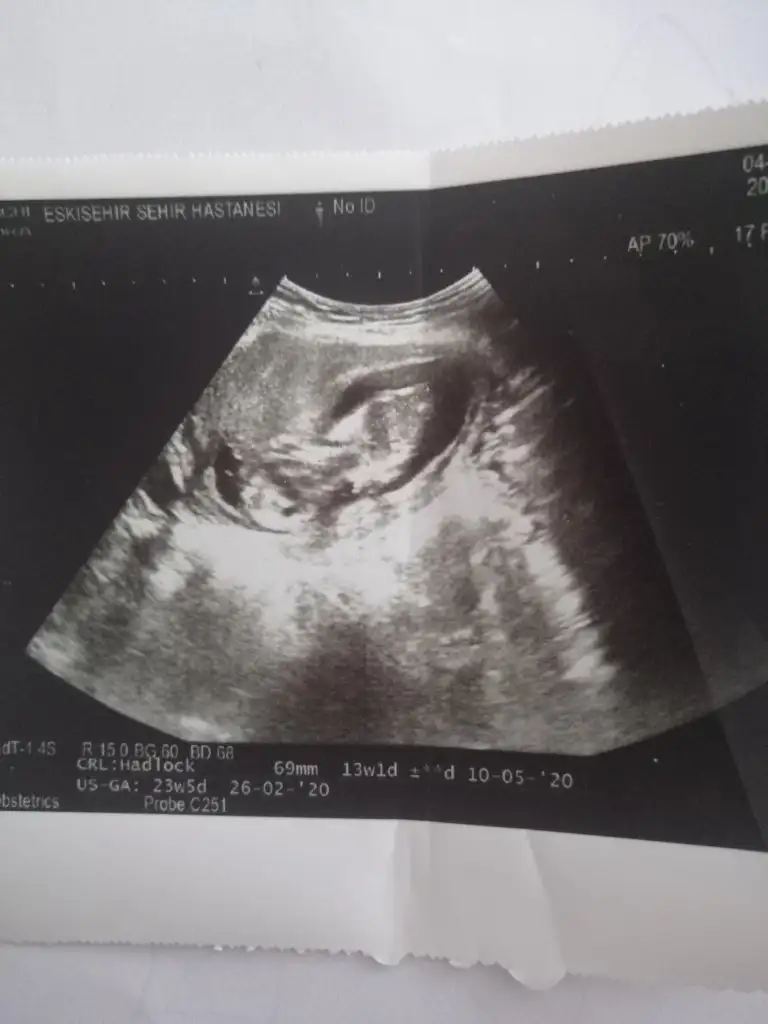

Banada erkek demiştiniz hatta baya net erkek demiştiniz kız diyince doktor şaşırmıştınız bnde çok şaşırmıştım tabi çünkü baya umutlanmıştım 2 kızım var doğal olarak değişik olsun istemiştim tabiki Rabbim in dediği olur ama hala erkek hissediyorum ayrıntılıda pozisyonu tersti cinsiyeti gözükmüyor demişti perinatolog ama 2 doktor kız gibi biride düşük kalitede bir cihazda kız demişti sonra rüyamda bebeğimin isminin koyulduğunu gördüm mavi nüfus kağıdında Ali arif yazıyordu bilemiyorum hala erkek hissediyorum pembe kıyafetleri almama rağmen

az kaldı sonucu görmeye herşey den önce Rabbim sağlıklı ve hayırlı evlatlar nasip etsin bizlere